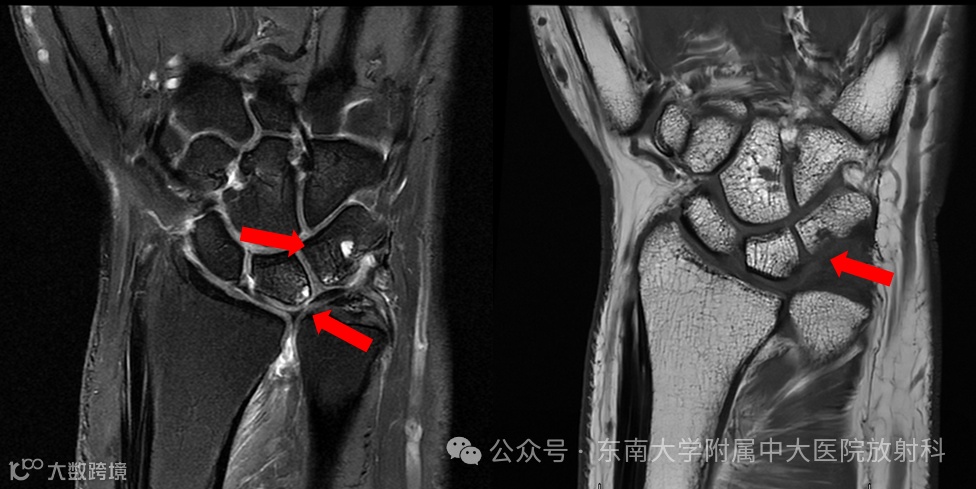

病例1

男 ,17岁

主诉:被撞伤致左腕关节肿痛半小时

病史:约半小时前患者骑车时被撞倒地,致右肘、左腕、双侧膝关节多处皮肤擦伤伴局部肿痛,受损关节活动稍受限,前来就诊

专科检查:左腕关节肿胀,局部压痛,左腕关节活动稍受限

影像号:3557176,2025-12-09,左腕关节正侧位X线、左腕关节CT平扫;影像号:3559976,2025-12-13,左腕关节MRI平扫

影像学表现